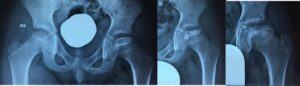

- Fase di frammentazione: il nucleo appare frammentato, “tigrato”, per riassorbimento delle trabecole necrotiche

- Fase di ricostruzione: il nucleo si ristruttura progressivamente

- Severità del coinvolgimento. Quest’ultimo viene valutato secondo la classificazione di Herring (o del pilastro laterale) che suddivide in gruppi a gravità crescente (A, B, B/C borderline, C) e prognosi progressivamente peggiore, a seconda del coinvolgimento della parte laterale dell’epifisi.